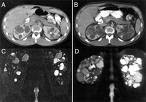

Polycystic Kidney Disease

Polycystic Kidney Disease is an autosomal dominant genetic disorder. It is the most frequent cause of renal failure among adults. It is also responsible for 6-8% of dialysis patients in the United States. Polycystic Kidney Disease is a multisystemic progressive disorder that is characterized by the formation and enlargement of renal cysts in the kidney and other adjacent abdominal organs such as: liver, pancreas, and spleen. It is also characterized by the bilateral cystic dilation of the renal tubules, which may lead to end-stage renal disease. Hepatic cysts, cerebral aneurysms, and cardiac valvular abnormalities are also possible. The disease can be classified either PKD1 and PKD2. PKD1 is expressed as an abnormality in the short arm of chromosome 16. PKD2 is expressed as an abnormality in the long arm of chromosome 4.

Ultrasound is the most widely accepted imaging technique for diagnosis of PKD because it does not use radiation or contrast material. It can diagnosis cysts up 1-1.5cm, as well as detect extrarenal abdominal features.

CT scan is a more sensitive imaging modality because it can detect renal cysts as small as 0.5cm but because of the use of radiation and contrast material it is not routinely used for diagnosis.

MRI is more sensitive than either ultrasound or CT, especially in determining the difference between PKD and Renal Cell Carcinoma. It is also the best imaging tool for monitoring kidney size after the patient has undergone treatment in order to assess progress.